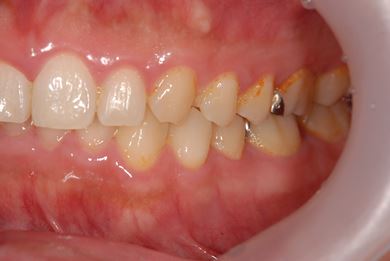

インプラントの症例写真 IMPLANT

抜歯即日スピードインプラント治療

| 性別/年齢 | 男性 / 38歳 | ||||||||||||||||||||||||||||||||

| 主訴 | 10年位前に虫歯治療をした右下奥歯のつめ物が取れ、再治療を受けた際にインプラントをすすめられたため、治療相談で来院。 | ||||||||||||||||||||||||||||||||

| 治療方針 | 抜歯と同時にインプラントを埋入し、治療期間を短縮する。 | ||||||||||||||||||||||||||||||||

| 治療内容 | インプラント1本(抜歯即日スピードインプラント)、ハイブリッドセラミッククラウン1本 | ||||||||||||||||||||||||||||||||